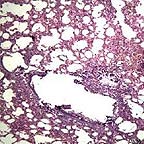

专家说法:对于患者的粗心,青岛京北肛肠医院李德明主任既痛心又无奈:通常我们对便血患者会格外警惕,除指检外,都会要求患者做电子肛门镜检查。李主任说,在电子肛门镜检查显示,在距肛门8㎝处,病灶呈“菜花状”,这是肠恶瘤典型表现症状。“前天早晨病理切片检验结果出来,证实患者患直肠恶瘤。”李主任说。

专家说法:据青岛京北医院吴修民主任介绍,肠息肉是引起便血的常见病之一。但需警惕的是直肠息肉又分为:腺瘤性息肉、炎性息肉 、增生性息肉和错构瘤。其中,腺瘤性息肉最常见但也最危险,因为结直肠腺瘤不及时治疗,可能发展为直肠癌。

“根据杨先生一年前的病历诊断,杨先生就是患了这种腺瘤性息肉。”吴主任说,可能接诊医生经验不足或过于疏忽,没有对腺瘤性息肉做出危害提醒,导致了患者的轻视大意。